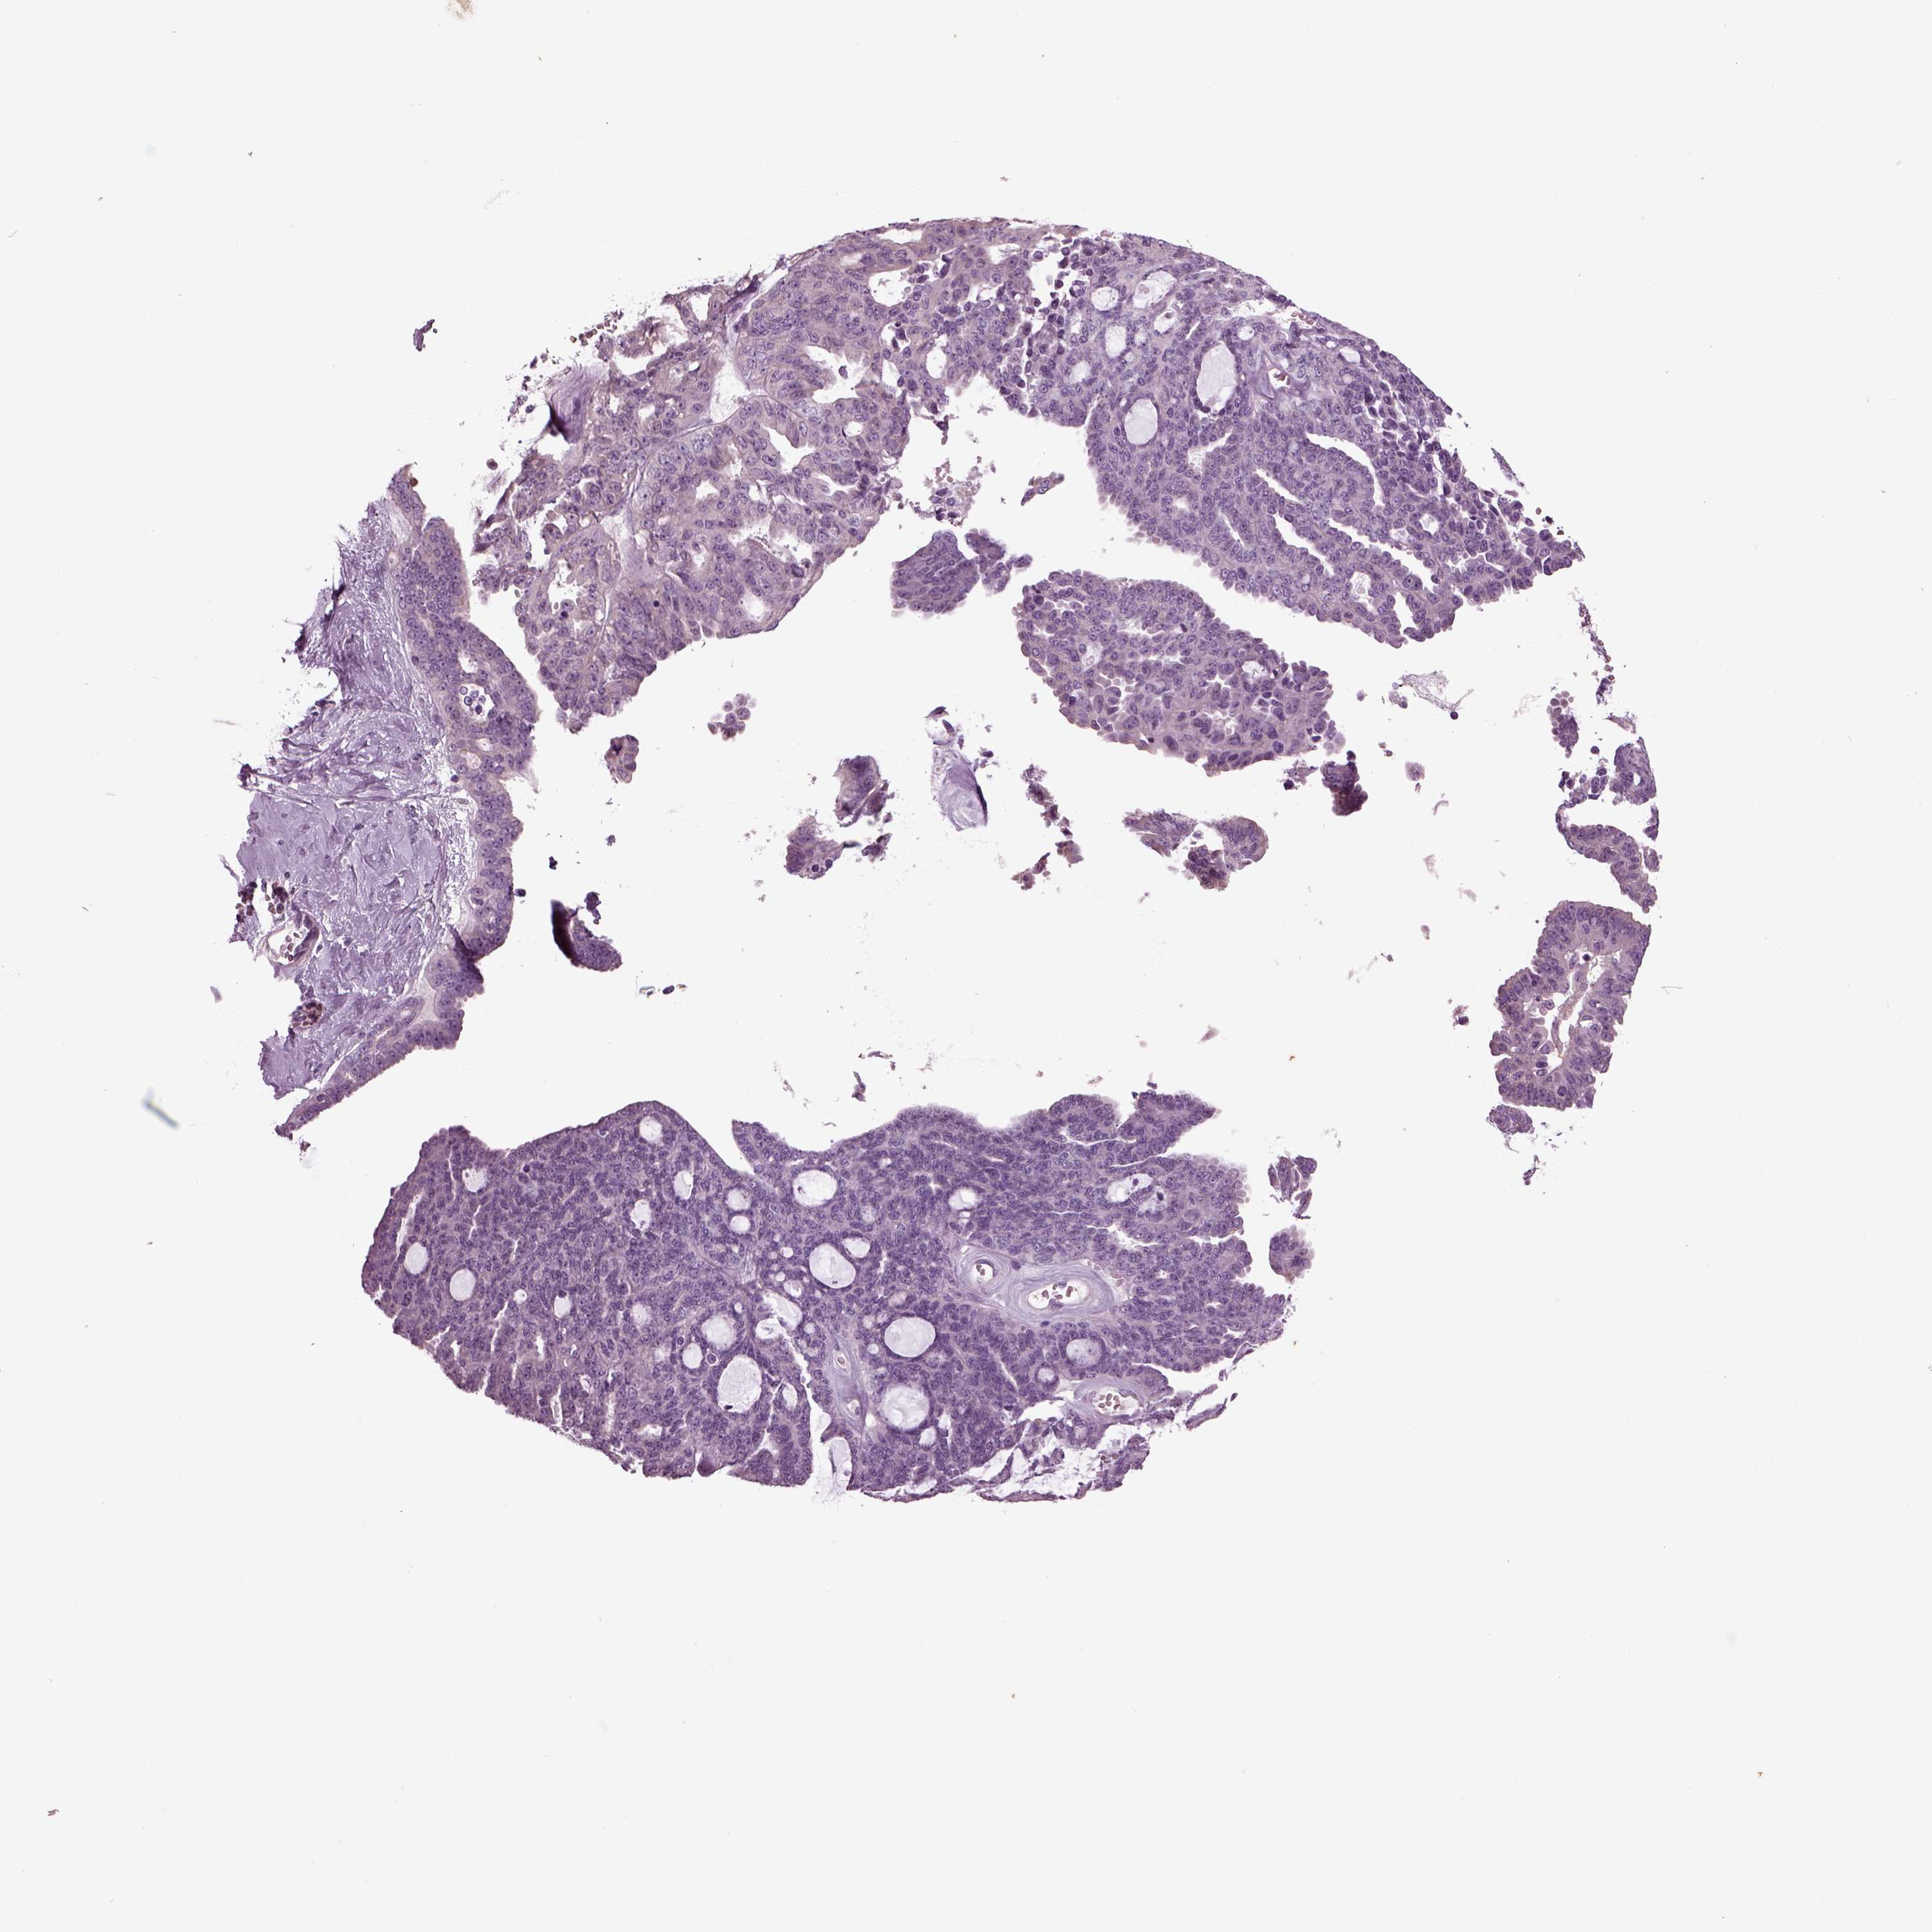

OVARIAN CANCER - Protein expressioni

A mouse-over function shows sample information and annotation data. Click on an image to view it in a full screen mode. Samples can be filtered based on level of antibody staining by selecting one or several of the following categories: high, medium, low and not detected. The assay and annotation is described here.

Note that samples used for immunohistochemistry by the Human Protein Atlas do not correspond to samples in the TCGA dataset.

Antibody stainingi

Antibody staining in the annotated cell types in the current human tissue is reported as not detected, low, medium, or high, based on conventional immunohistochemistry profiling in selected tissues. This score is based on the combination of the staining intensity and fraction of stained cells.

Each image is clickable and will lead to virtual microscopy that enables deeper exploration of all samples and also displays staining intensity scores, fraction scores and subcellular localization as well as patient and tissue information for each sample.

Antibody HPA008759

Antibody HPA012602

Antibody CAB009403

Cystadenocarcinoma, serous, NOS

Cystadenocarcinoma, mucinous, NOS

Carcinoma, endometroid